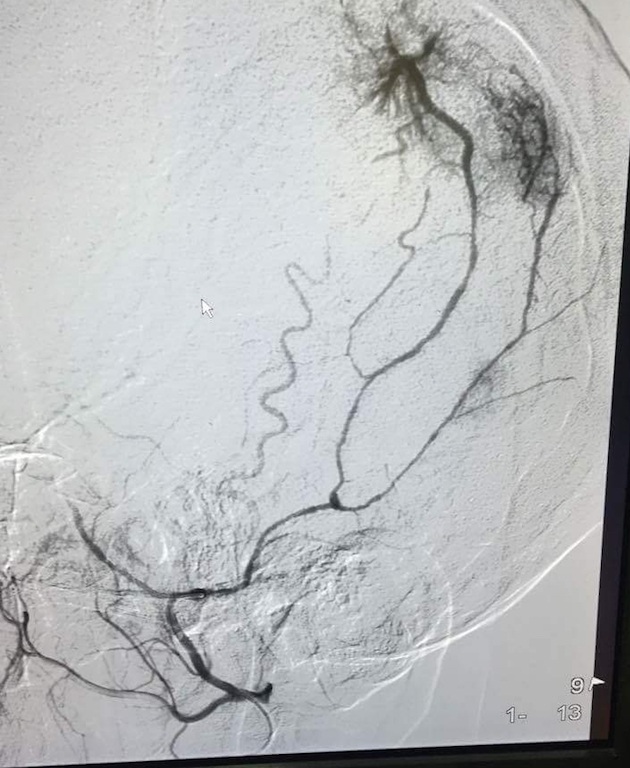

Ngày 22/9, ê kíp can thiệp mạch của khoa thần kinh đã tiến hành chụp mạch cho bệnh nhân để đánh giá mạch máu nuôi và tác động mạch nuôi khối u não. Từ đó, êkip xác định rõ động mạch màng não giữa cung cấp lượng lớn máu nuôi u.

“Chúng tôi sử dụng một ống siêu nhỏ, luồn từ động mạch đùi, tại vị trí cuống mạch nuôi khối u, các hạt vật liệu được bơm vào mạch máu, làm giảm dần khẩu kính lòng mạch và cuối cùng gây tắc mạch. Nút mạch trước mổ làm giảm lượng máu tới u,hạn chế nguy cơ chảy máu ồ ạt trong phẫu thuật; đồng thời làm khối u hoại tử dần, thời gian phẫu thuật được rút ngắn, tăng tính an toàn cho người bệnh”, Bác sỹ Lê Quang Toàn, khoa thần kinh cho biết.